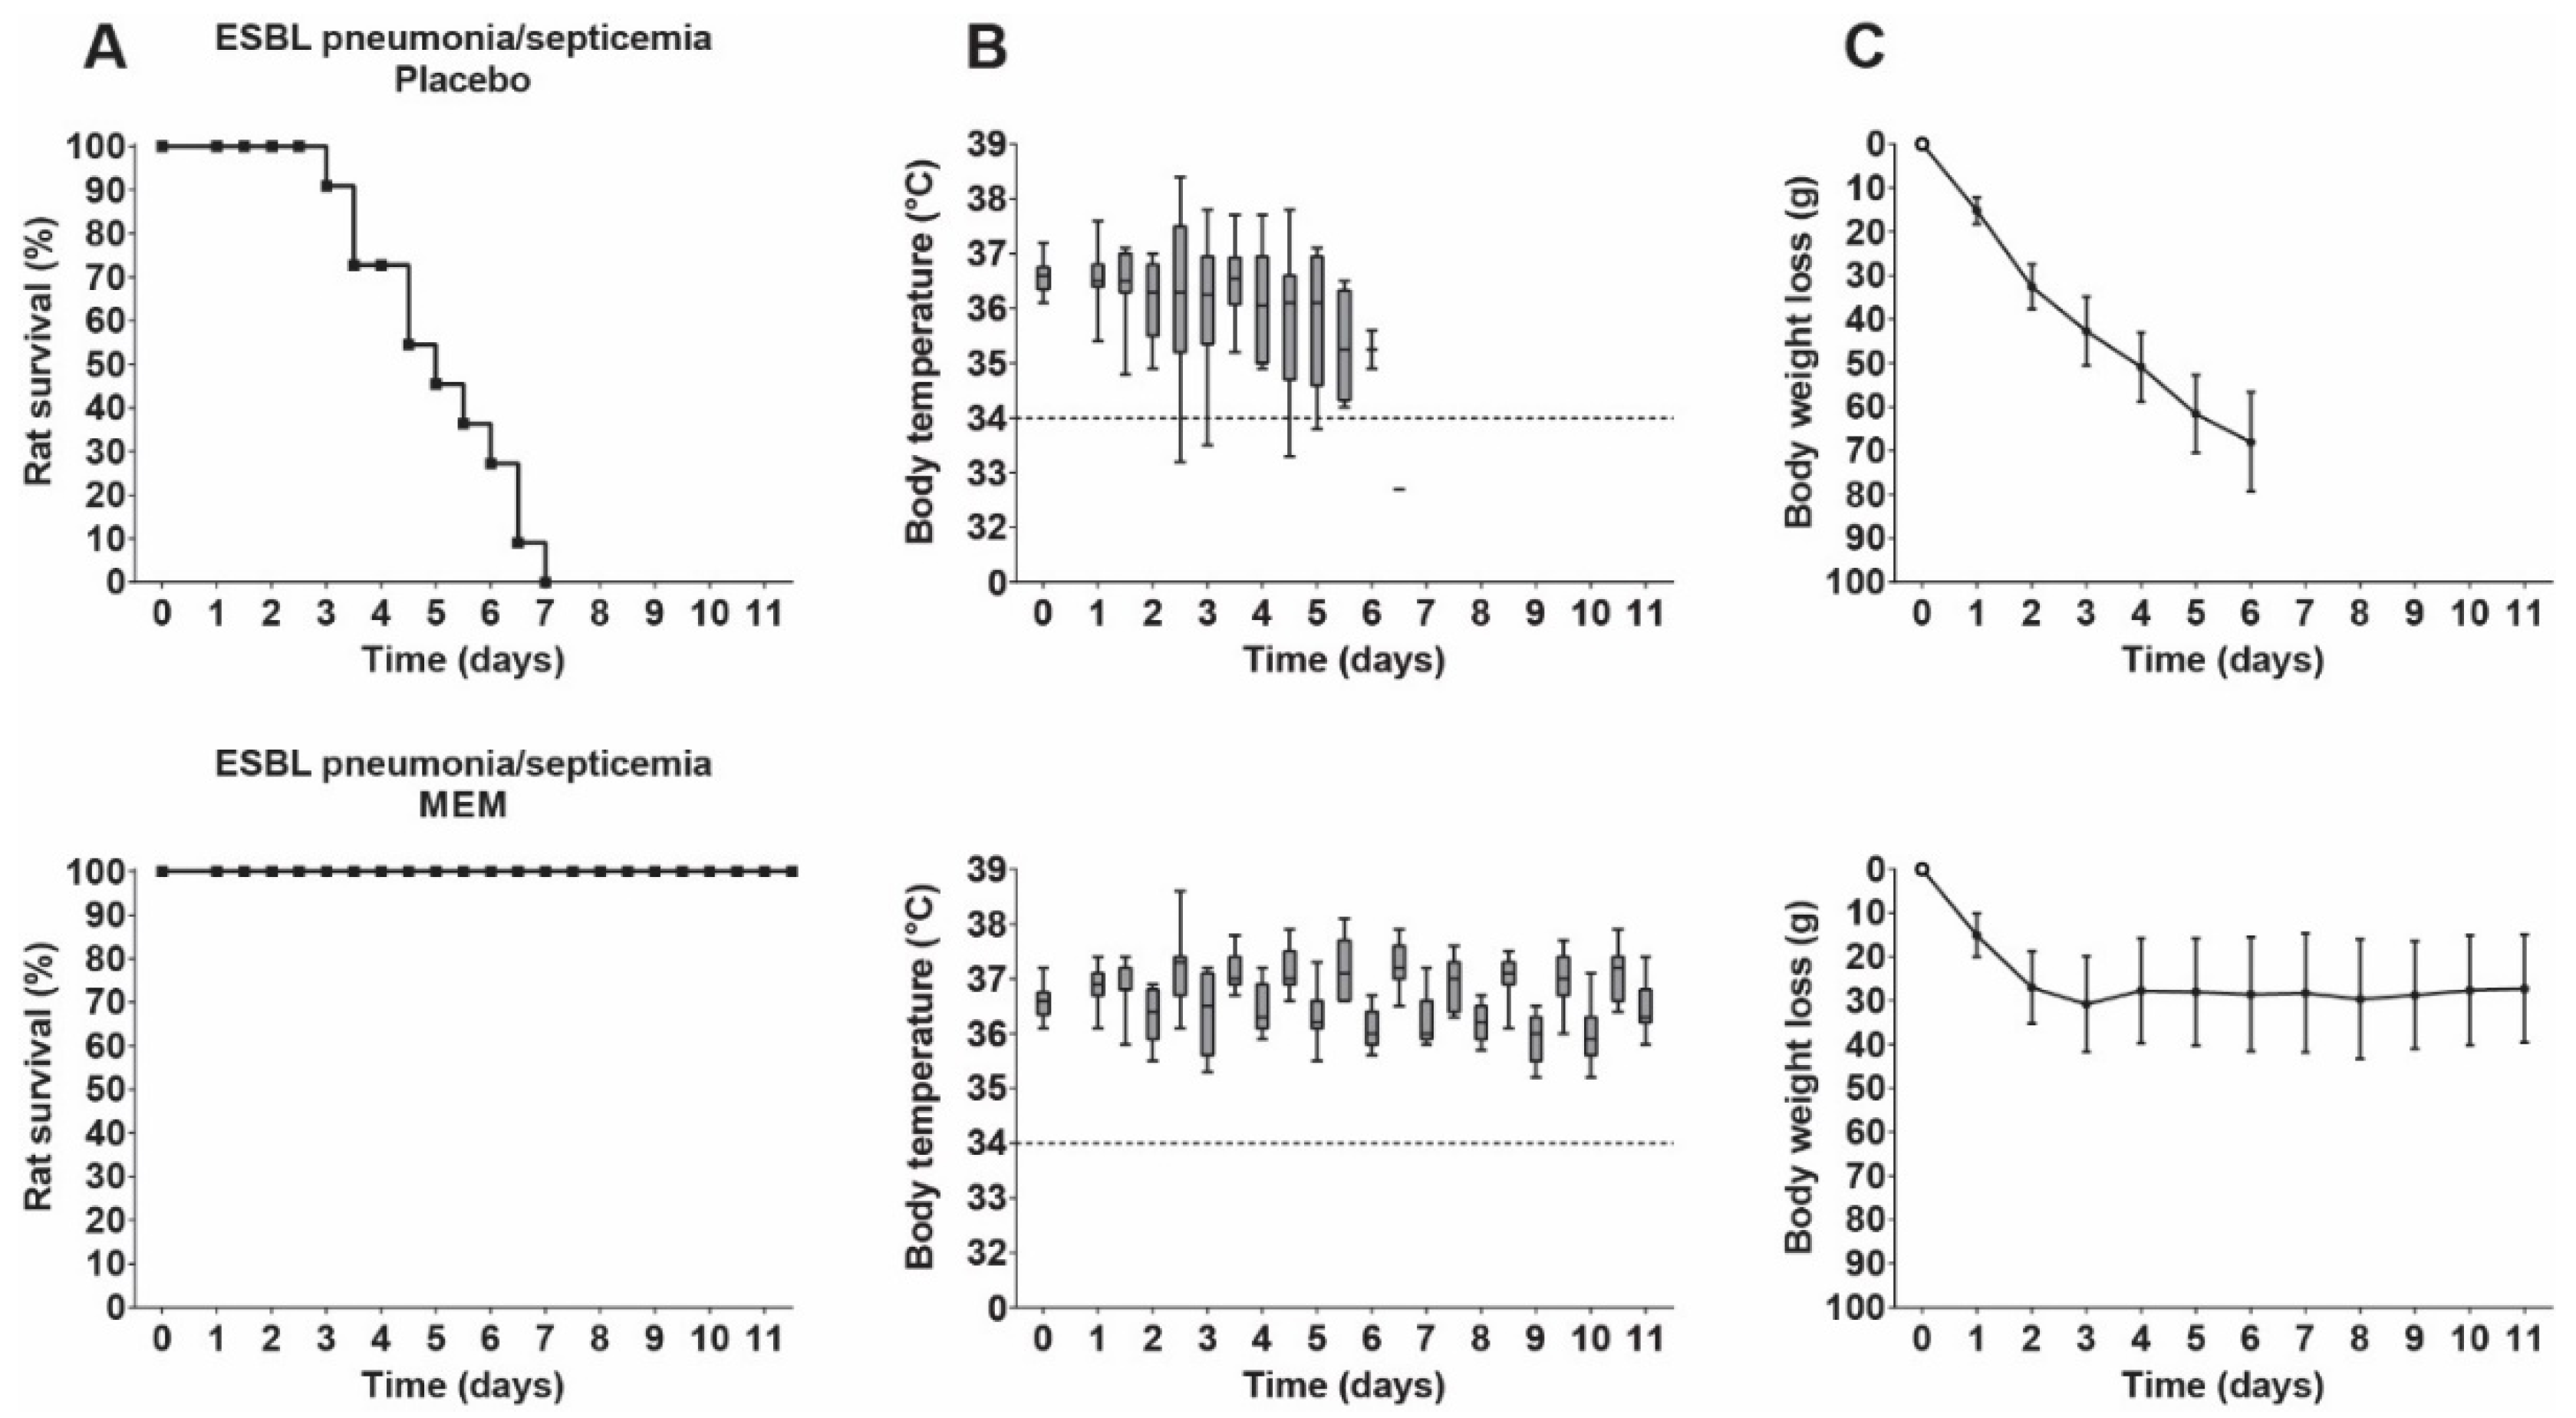

3.5. Therapeutic Efficacy of Meropenem in Rats with ESBL Pneumonia–Septicemia